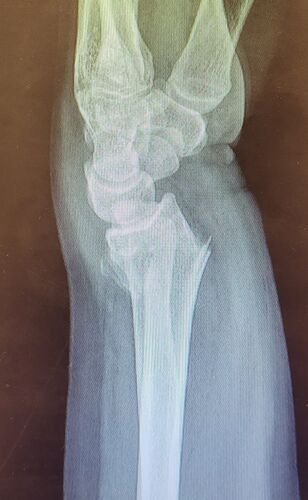

Meu nome e Isabella, mais conhecida como Snow, eu estava andando de muleta e a borracha dela saiu e eu tenho problema de equilibrio devido ao meu femur, bati o osso e piorou a situação, tive o radio do braço afetado e colocaram pino e deram um jeito de reverter porque eu ficaria com movimento do braço e mão comprometidos, tive traumatismo craniano porque bati a cabeça, esse ano eu já tinha sofrido um depois de um aparelho de raio x cair na testa mas fiquei sem sequelas na cabeça. Bom como muitos que me acompanham eu tenho uma condição rara entre mulheres que eu tenho os ossos do fêmur necrosados em mais de 75% desde 2022, eu sofri um acidente hoje andando de muleta, machuquei o fêmur, rosto, tivd que operar porque era uma emergência, não tenho muitas fotos pois estava internada mas tentei no SUS e não tinha pino de titânio,meu caso era de extrema urgência, eu to vendendo tudo e abrindo mão ate do meu apartamento pra cobrir a cirurgia e tenho ate final de setembro pra bater pelo menos 20 mil de meta, tenho inúmeras vakinhaa mostrando minha real doença autoimune e uma delas sendo rara que é osteonecrose bilateral do fêmur, o tratamento tá sendo todo particular mesmo sendo paciente do hospital das clínicas, ainda e difícil e nem sempre consigo as coisas, eu tento de todas formas é isso ainda pode me prejudicar na minha carreira, detesto pedir ajuda mas não tenho opção, a comunidade da minha área entre outros interesses sempre me apoiaram e infelizmente veio com humildade e de cabeça baixa pedir ajuda, faz tempo que tento recomeçar minha carreira desde o diagnóstico e nunca desisti dos meus sonhos e cirurgia

Vou deixar imagem atual do acidente abaixo e de algumas vakinhas anteriores